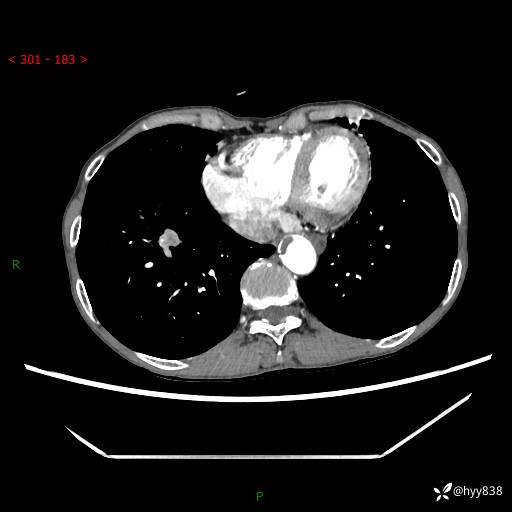

69岁/女,发现肺占位3天余。精彩好病例,请慧诊---(有结果)

【患者信息】:69岁/女

【主诉】:发现肺占位3天余

【现病史及既往史】:患者3天余前因既往肺气肿复查胸部CT发现“右肺下叶结节、双肺多发结节、双肺门及纵膈淋巴结增大”,平素偶有咳白色粘液痰,下肢乏力,无明显低热、盗汗、咯血、胸痛、喘气等不适,今为求明显结节性质遂来我院门诊就诊,门诊以“孤立性肺结节”收治入院。 起病以来,患者精神饮食睡眠一般,大小便正常,体力无明细变化,体重近年来较前下降。

【检查】:胸部CT增强